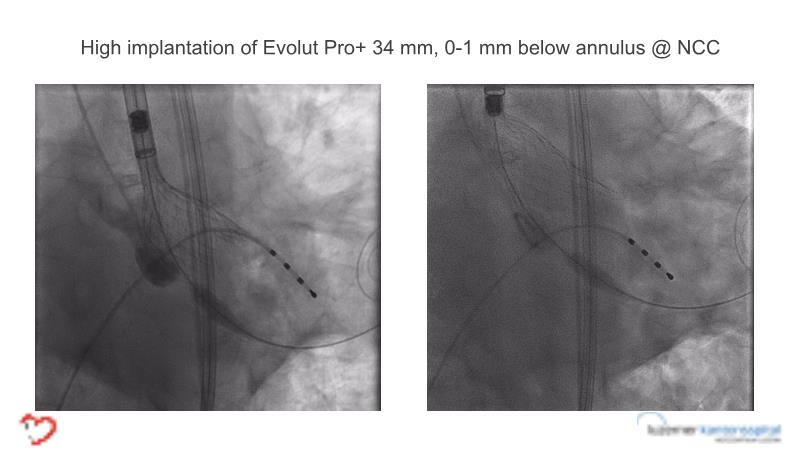

- To learn tips and tricks for managing bicuspid and valve-in-valve interventions